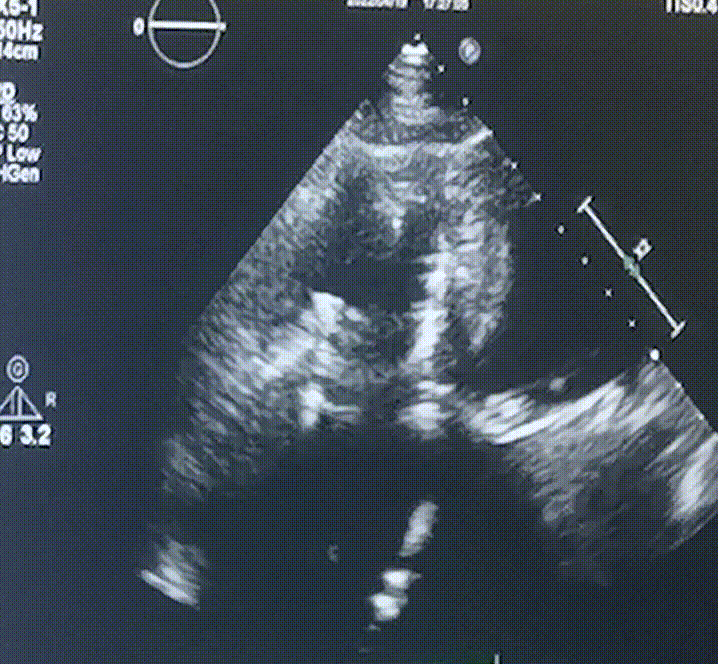

此次手術(shù)在全麻下進行,采用經(jīng)右側(cè)頸靜脈入路。術(shù)中在經(jīng)食道超聲和DSA的指引下多個維度精細調(diào)整輸送器角度,在達到正確位置后,逐步釋放瓣膜錨定裝置和盤片,最終完成瓣膜植入。術(shù)后患者右房壓明顯下降,術(shù)后超聲提示人工三尖瓣同軸性良好,瓣架固定牢靠,無反流和瓣周漏,血壓術(shù)后即刻上升20mmHg左右,手術(shù)后監(jiān)護室順利拔除氣管插管,3天后恢復(fù)良好,予以出院。

圖2.術(shù)后超聲